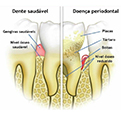

A doença periodontal é uma doença que vem de maneira silenciosa, levando vários anos de evolução, até a perda do dente sem o paciente perceber. Inicia-se com uma gengiva inflamada, com sangramento ao escovar e uso do fio dental. É conhecida como gengivite. A gengivite não tratada leva ao aparecimento da periodontite, onde há uma destruição do osso de sustentação, levando à mobilidade e consequentemente a perda dos dentes. Portanto, a prevenção e o tratamento da gengivite reduzem o risco de desenvolvimento da periodontite. Na foto abaixo podemos ver o lado esquerdo sem doença periodontal e o lado direito com os tártaros e uma grande destruição óssea.